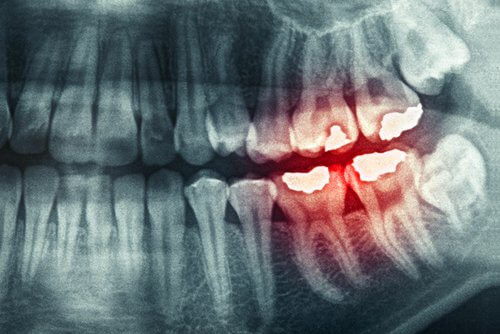

1-Bruxism

Bruxism is a problem that affects more people than expected. This is when you clench or grind your teeth, while you’re awake or asleep. In the most extreme cases a mouth guard is required. Without it, you could end up really damaging your teeth.

The best thing in these cases is to talk not only with a dentist — who can provide you a mouth guard — but with a psychologist as well. It’s important to locate the tension that you feel during the night when you grind your teeth.